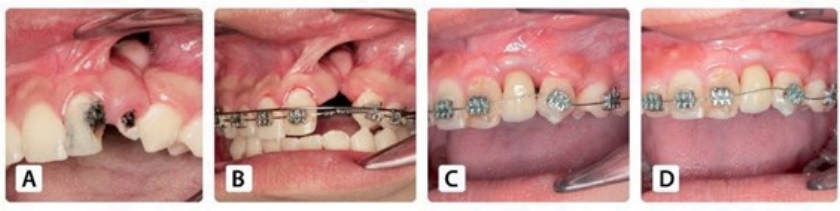

Công trình nghiên cứu “A New Technique of Two Iliac Cortical Bone Blocks Sandwich Technique for Secondary Alveolar Bone Grafting in Cleft Lip and Palate Patients” của Tiến sĩ, Bác sĩ Võ Văn Nhân và cộng sự đã được thực nghiệm với sự tham gia của 32 bệnh nhân mắc phải tình trạng khe hở môi vòm miệng (bao gồm 23 nữ, 9 nam).

Trên thực tế, phẫu thuật cấy ghép implant cho bệnh nhân khe hở môi vòm miệng được đánh giá khá phức tạp, khó có thể đạt được kết quả như mong muốn do tính ổn định không cao. Tuy nhiên, Ts.Bs Võ Văn Nhân và cộng sự đã nghiên cứu và thử nghiệm lâm sàng cho bệnh nhân kỹ thuật mới trong ghép xương và cấy ghép implant.

So với những kỹ thuật trước đây, kỹ thuật này đã có sự đột phá vượt trội. Điều này được giải thích bởi hai lí do. Thứ nhất, nhóm nghiên cứu đã sử dụng hai mảnh xương mào chậu để giúp vết thương lành nhanh chóng cũng như tránh được sự tiêu xương sau này. Thứ hai, các bác sĩ đã thực hiện kỹ thuật làm tăng độ ổn định ban đầu khi cấy implant như lỗ khoan xương nhỏ, implant được xử lí bề mặt tốt hơn, từ đó đảm bảo được độ an toàn, giúp quá trình cấy ghép implant diễn ra thành công.

Ts.Bs Võ Văn Nhân cho biết: “Công trình nghiên cứu đã ghi nhận tỷ lệ tồn tại của implant là 100%. Tất cả bệnh nhân đều hài lòng với phục hình trên implant và đạt 71,9% phục hình từ ngưỡng chấp nhận lâm sàng trở lên theo tiêu chuẩn của Belser”.